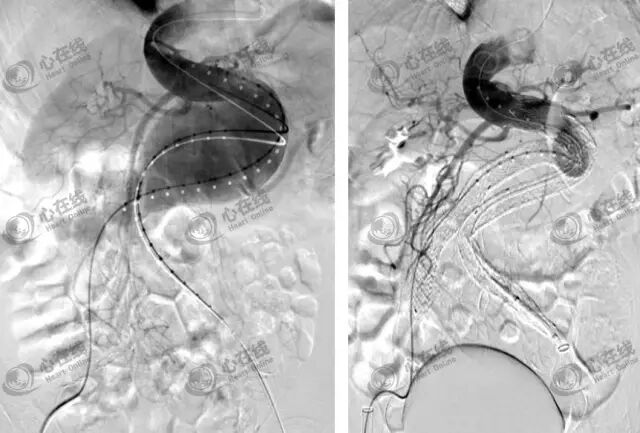

(5)血管造影

血管造影为诊断金标准,血管腔内腹主动脉瘤修复(EVAR)术中常规显示主动脉腔及分支血管病变,可指导治疗策略选择。

传统EVAR需满足:近端瘤颈长度≥1.5cm、夹角≤600、髂股动脉直径≥7.5mm、瘤颈无严重钙化或附壁血栓等条件。

3.EVAR进展